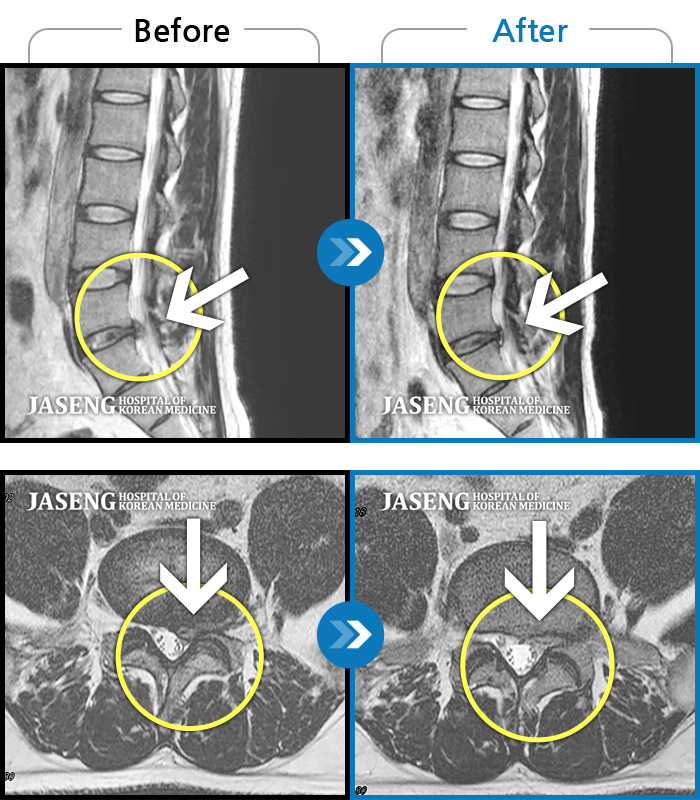

• 허리디스크